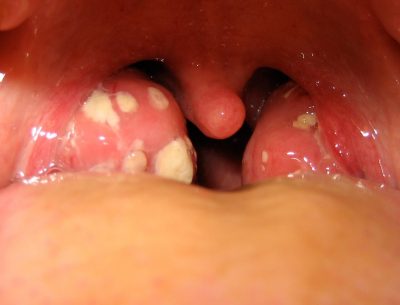

Tıkayıcı bademcik büyümesi apne (nefes tutma) veya büyüme-gelişme geriliği ile birlikte... Bademcikte tekrarlayan kanama tekrarlayan... ...